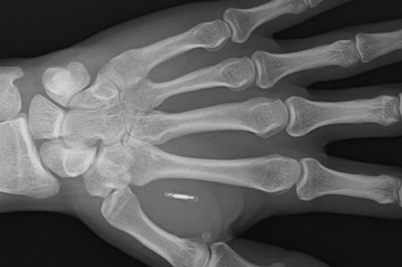

Biohacker非接触式支付芯片生物黑客PatrickPaumen最近在他不断增长的一系列增强功能中添加了一个新的微芯片植入物,现在总共有32个生物植入物,其中现在包括一个非接触式支付芯片,让他无需使用智能手机或钱包即可轻松方便地支付物品.

“这是因为这位37岁的老人不需要使用银行卡或手机支付。相反,他只需将左手放在非接触式读卡器附近,即可完成付款。“我从收银员那里得到的反应是无价的!”来自荷兰的保安Paumen先生说。他能够用手支付,因为早在2019年,他的皮肤下就注射了一个非接触式支付微芯片。“这个过程就像有人捏你的皮肤一样疼,”波门先生说。